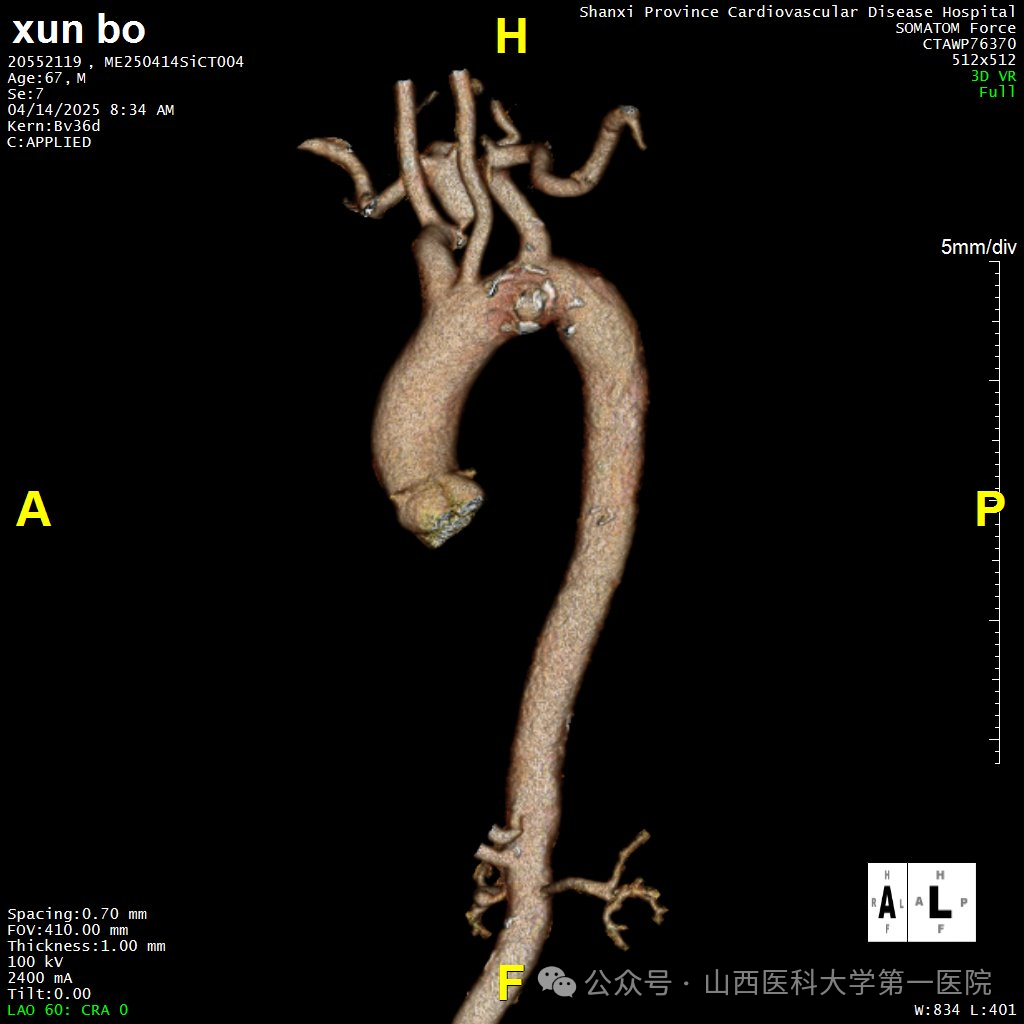

67岁男性患者既往有高血压病史,因反复胸背部不适入院。CTA检查提示其降主动脉左锁骨下动脉开口水平处存在一处穿透性溃疡,病灶大小约为1.9×1.0cm,穿透性溃疡位置累及左锁骨下动脉,主动脉穿透性溃疡可能发展成主动脉夹层、主动脉破裂,危及生命。

术前CTA